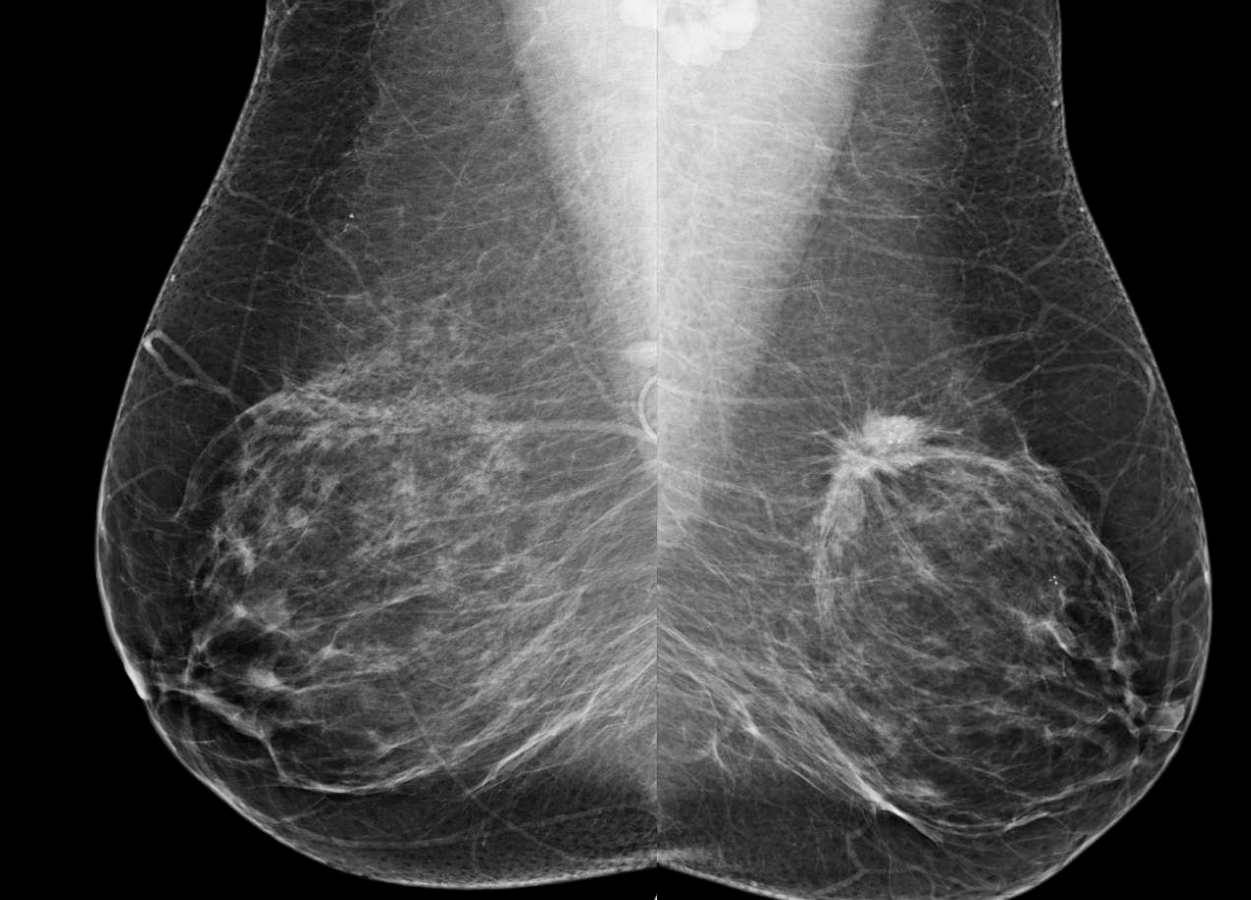

Mammography Screening Intervals May Affect Breast Cancer ... 😈